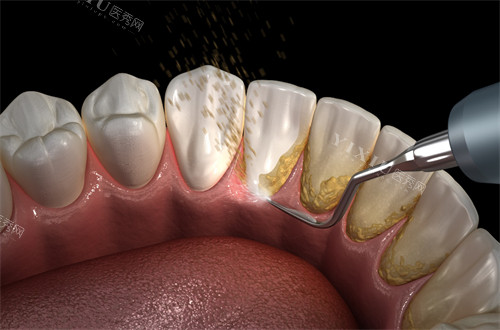

三、补牙修复:从基础树脂到高端瓷贴面,满足多元修复需求

(一)树脂补牙

树脂材料因美观耐用成为主流选择:

国产树脂:浅龋补牙260元起,中龋380元起,深龋580元起,适合预算有限的患者。

进口树脂:美国3M-Z250树脂298元起,3M-P60树脂559元起,德国VOCO树脂439元起,耐磨性与色泽更优。

(二)嵌体/冠修复

重度缺损牙齿需采用嵌体或牙冠保护:

嵌体补牙:1600元起,根据牙洞定制,严丝合缝减少二次龋坏。

疑问解答:针对消费者对“补牙价格差异大”的疑问,爱齿口腔解释称,价格差异主要源于材料性能(如进口树脂耐磨性比国产高30%)、术式复杂度(如深龋需垫底治疗)及医生技术附加值。所有项目均明码标价,无隐形消费。